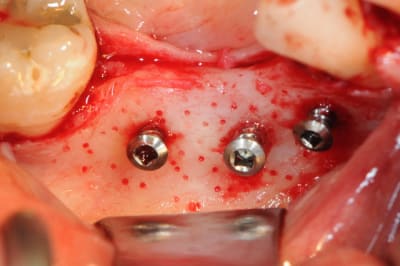

CAS 1

demande de restauration avec implant, mais, ne veut pas entendre parler de greffes et greffons.

la ROG lui semble plus "naturel".

4 après ouverture

7-8: et voilà 3 vis qui vont maintenir ma membrane au dessus de l'os.